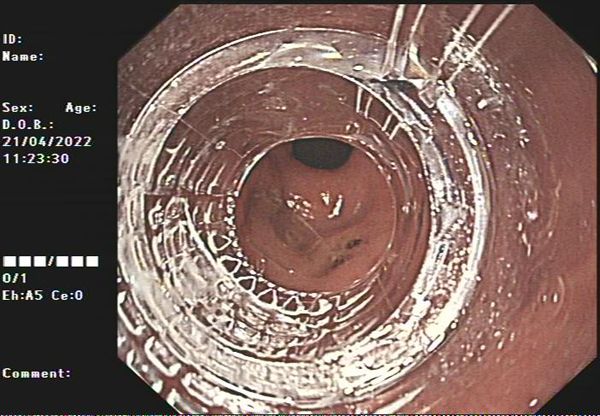

内镜科详细了解病情对其进行综合检查,发现患者吞食塑料纸片面积大,质地较韧,且呈尖角状,十分危险,立即请麻醉团队会诊,对患者的病情进行详细评估和讨论,做好术中、术后的各种风险预案,在与患者及其家属充分沟通后,由副院长、内镜科主任张亚飞行内镜下异物取出术,后在无痛胃镜透明帽辅助下异物顺利被取出。

术后,张亚飞副院长对患者再次进镜检查上消化道情况,发现患者胃窦已形成多处明显溃疡,幸好及时将异物取出,避免了进一步消化道穿孔的可能。